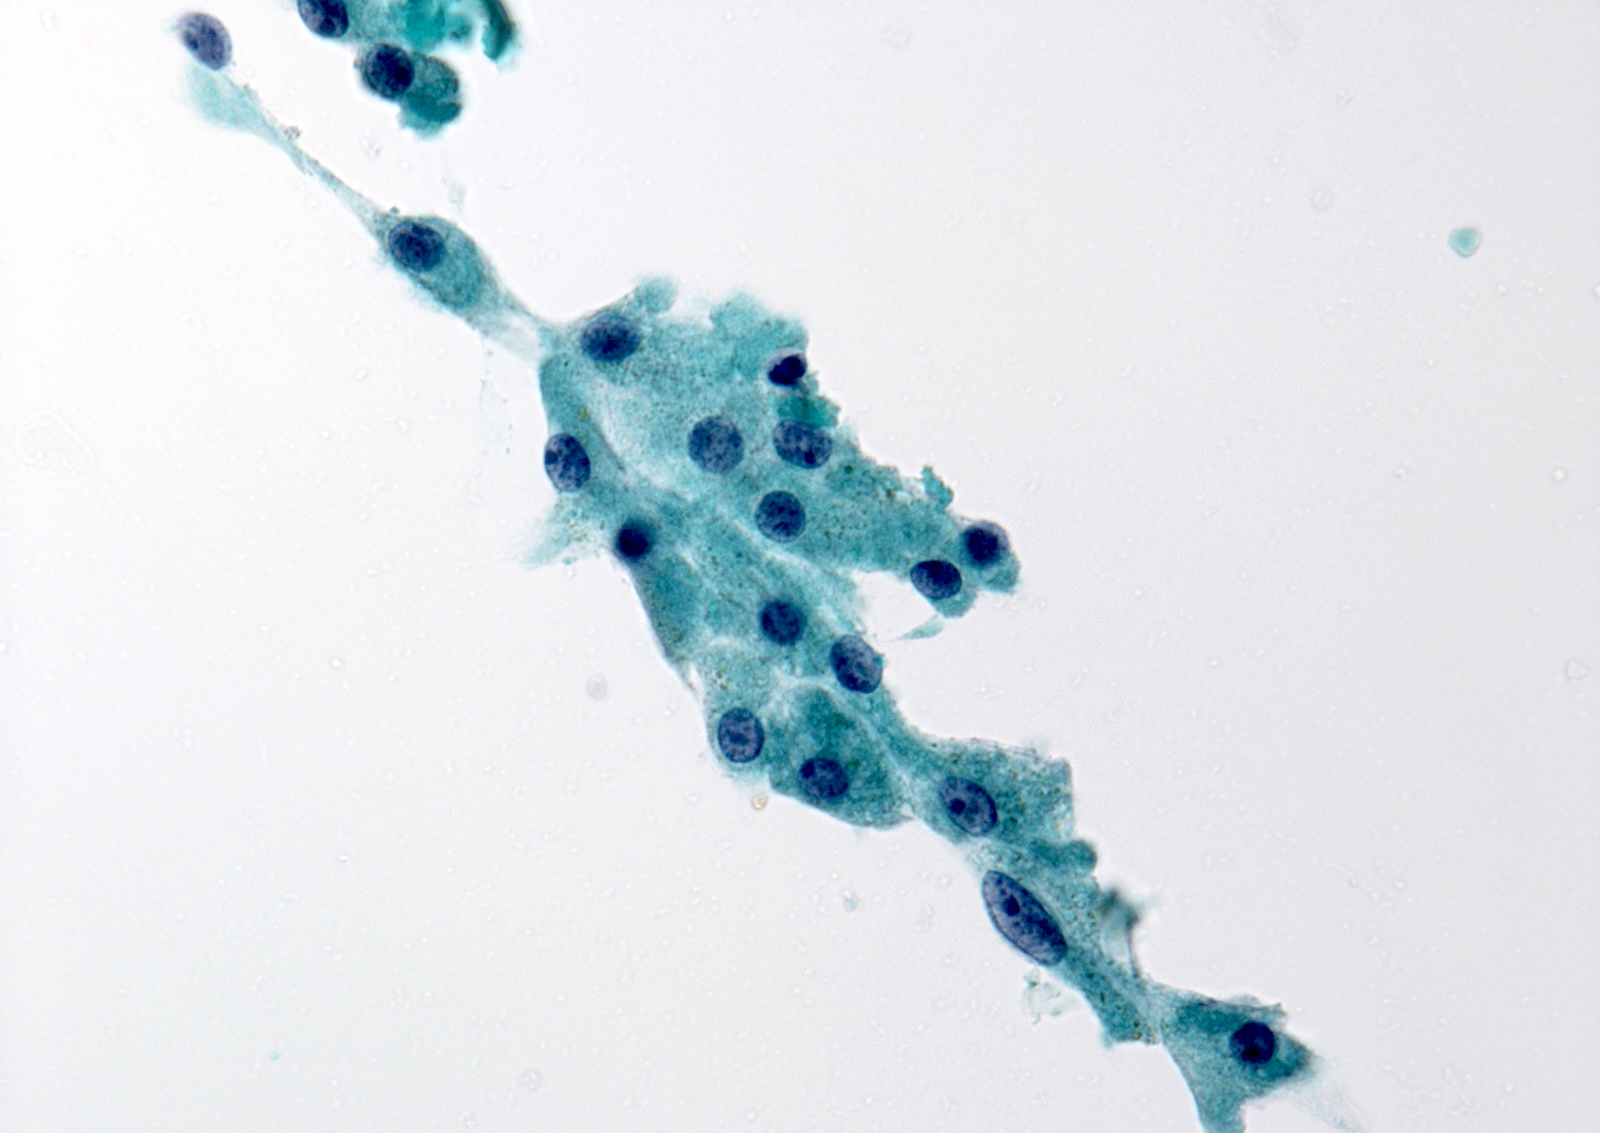

Cytology images

Contributed by Ayana Suzuki, Ph.D.

- Atypical cyst lining cells:

- Cyst lining cells may appear atypical (rare cases), such as

- Nuclear grooves

- Prominent nucleoli

- Elongated nuclei and cytoplasm

- Rare intranuclear pseudoinclusions

- Associated with hemosiderin laden macrophages

- Reactive follicular or mesenchymal cells associated with cystic degeneration of thyroid nodules

- Most cases are benign (Cancer 2005;105:71)